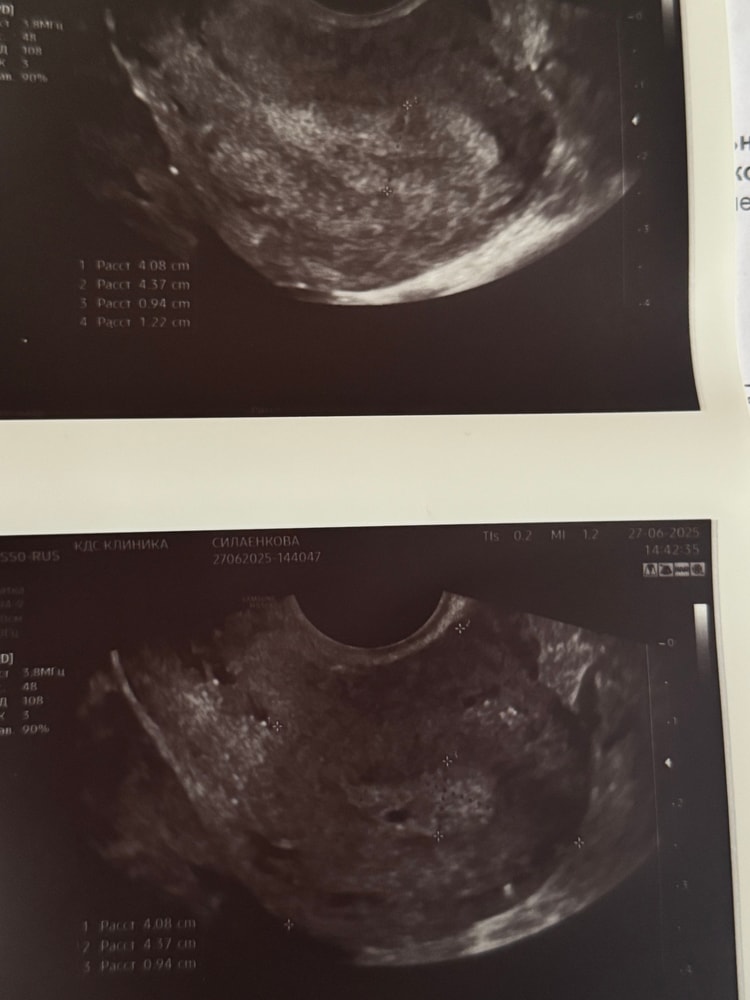

Вот моя узишка